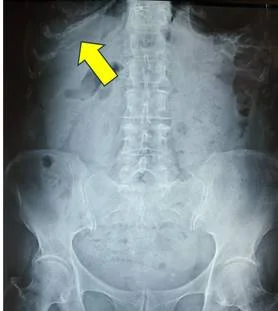

Например, накопление кальция в хрящах грудной клетки (синдроме Титце) может привести к боли воспалительного характера в грудной клетке. Особенно в области грудины. И это не означает, что имеет место инфаркт или атеросклероз сосудов сердца. Синдром Тице – свидетельствует о нарушение кальциевого обмена и проявляется накоплением кальция в реберных хрящах (обозначено желтой стрелкой). Это может сопровождаться болью в области грудины за счет накопления кальция в суставах грудной клетки, что сопровождается болью.